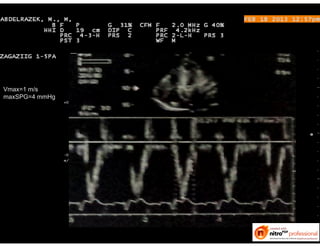

Vmax=1 m/s

maxSPG=4 mmHg